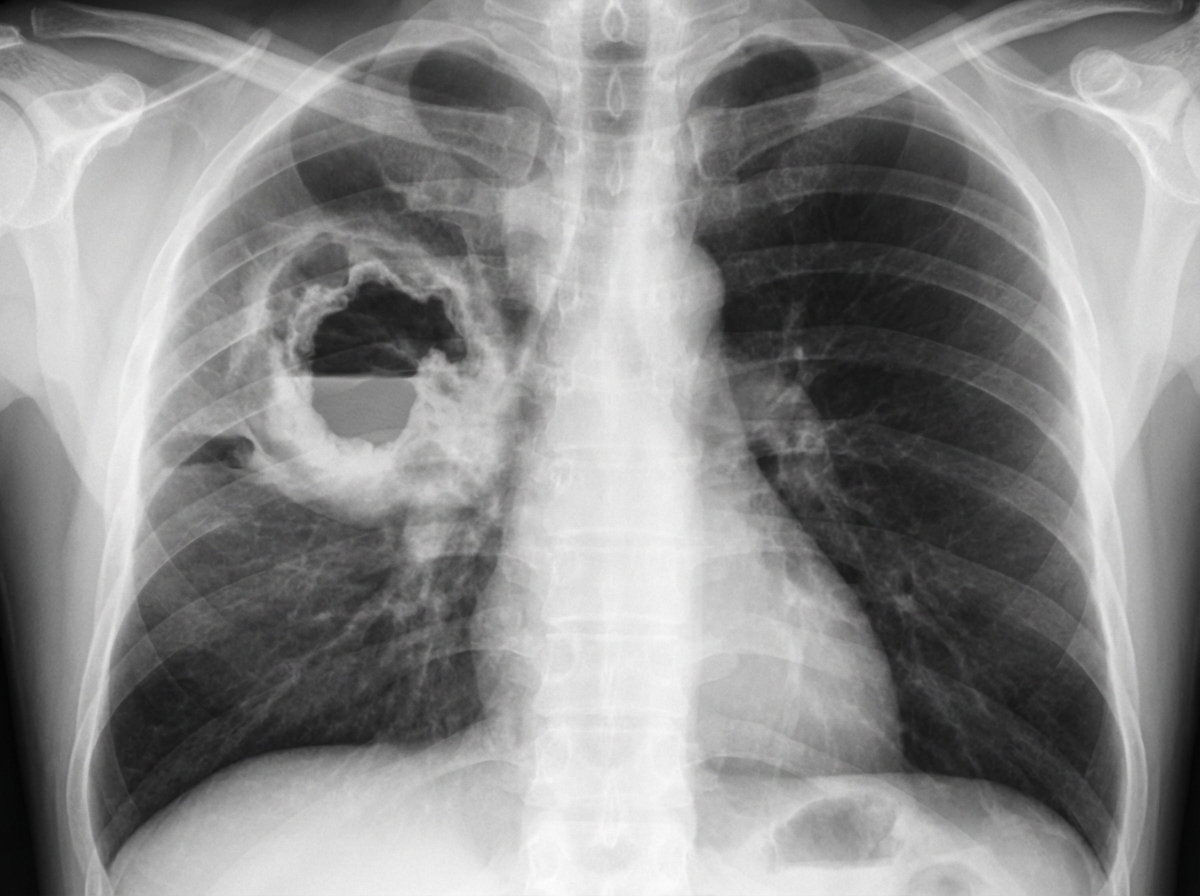

A 65-year-old woman presents to her physician with a persistent and debilitating cough which began 3 weeks ago, and chest pain accompanied by shortness of breath for the past week. Past medical history is significant for breast carcinoma 10 years ago treated with mastectomy, chemotherapy and radiation, a hospitalization a month ago for pneumonia that was treated with antibiotics, hypertension, and diabetes mellitus. Medications include chlorthalidone and metformin. She does not smoke but her husband has been smoking 3 packs a day for 30 years. Today her respiratory rate is 20/min and the blood pressure is 150/90 mm Hg. Serum Na is 140 mmol/L, serum K is 3.8 mmol/L and serum Ca is 12.2 mg/dL. A chest X-ray (shown in image) is performed. Which of the following is the most likely diagnosis?